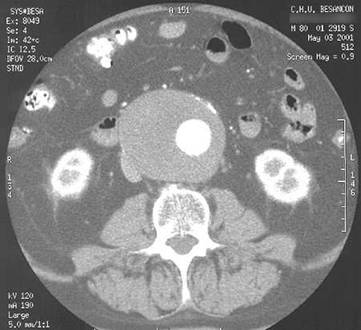

Anevrism de aorta abdominala sub renale intinsa la arterele iliace

primitive.

Voluminos anevrism de aorta abdominala sub renale cu important tromb mural

si fine calcificari periferice anterioare. Scanner de aorta abdominala.

Cupe axiale cu injectare i.v. de produs de contrast iodat.

Lumenul arterial rezidual este excentric.